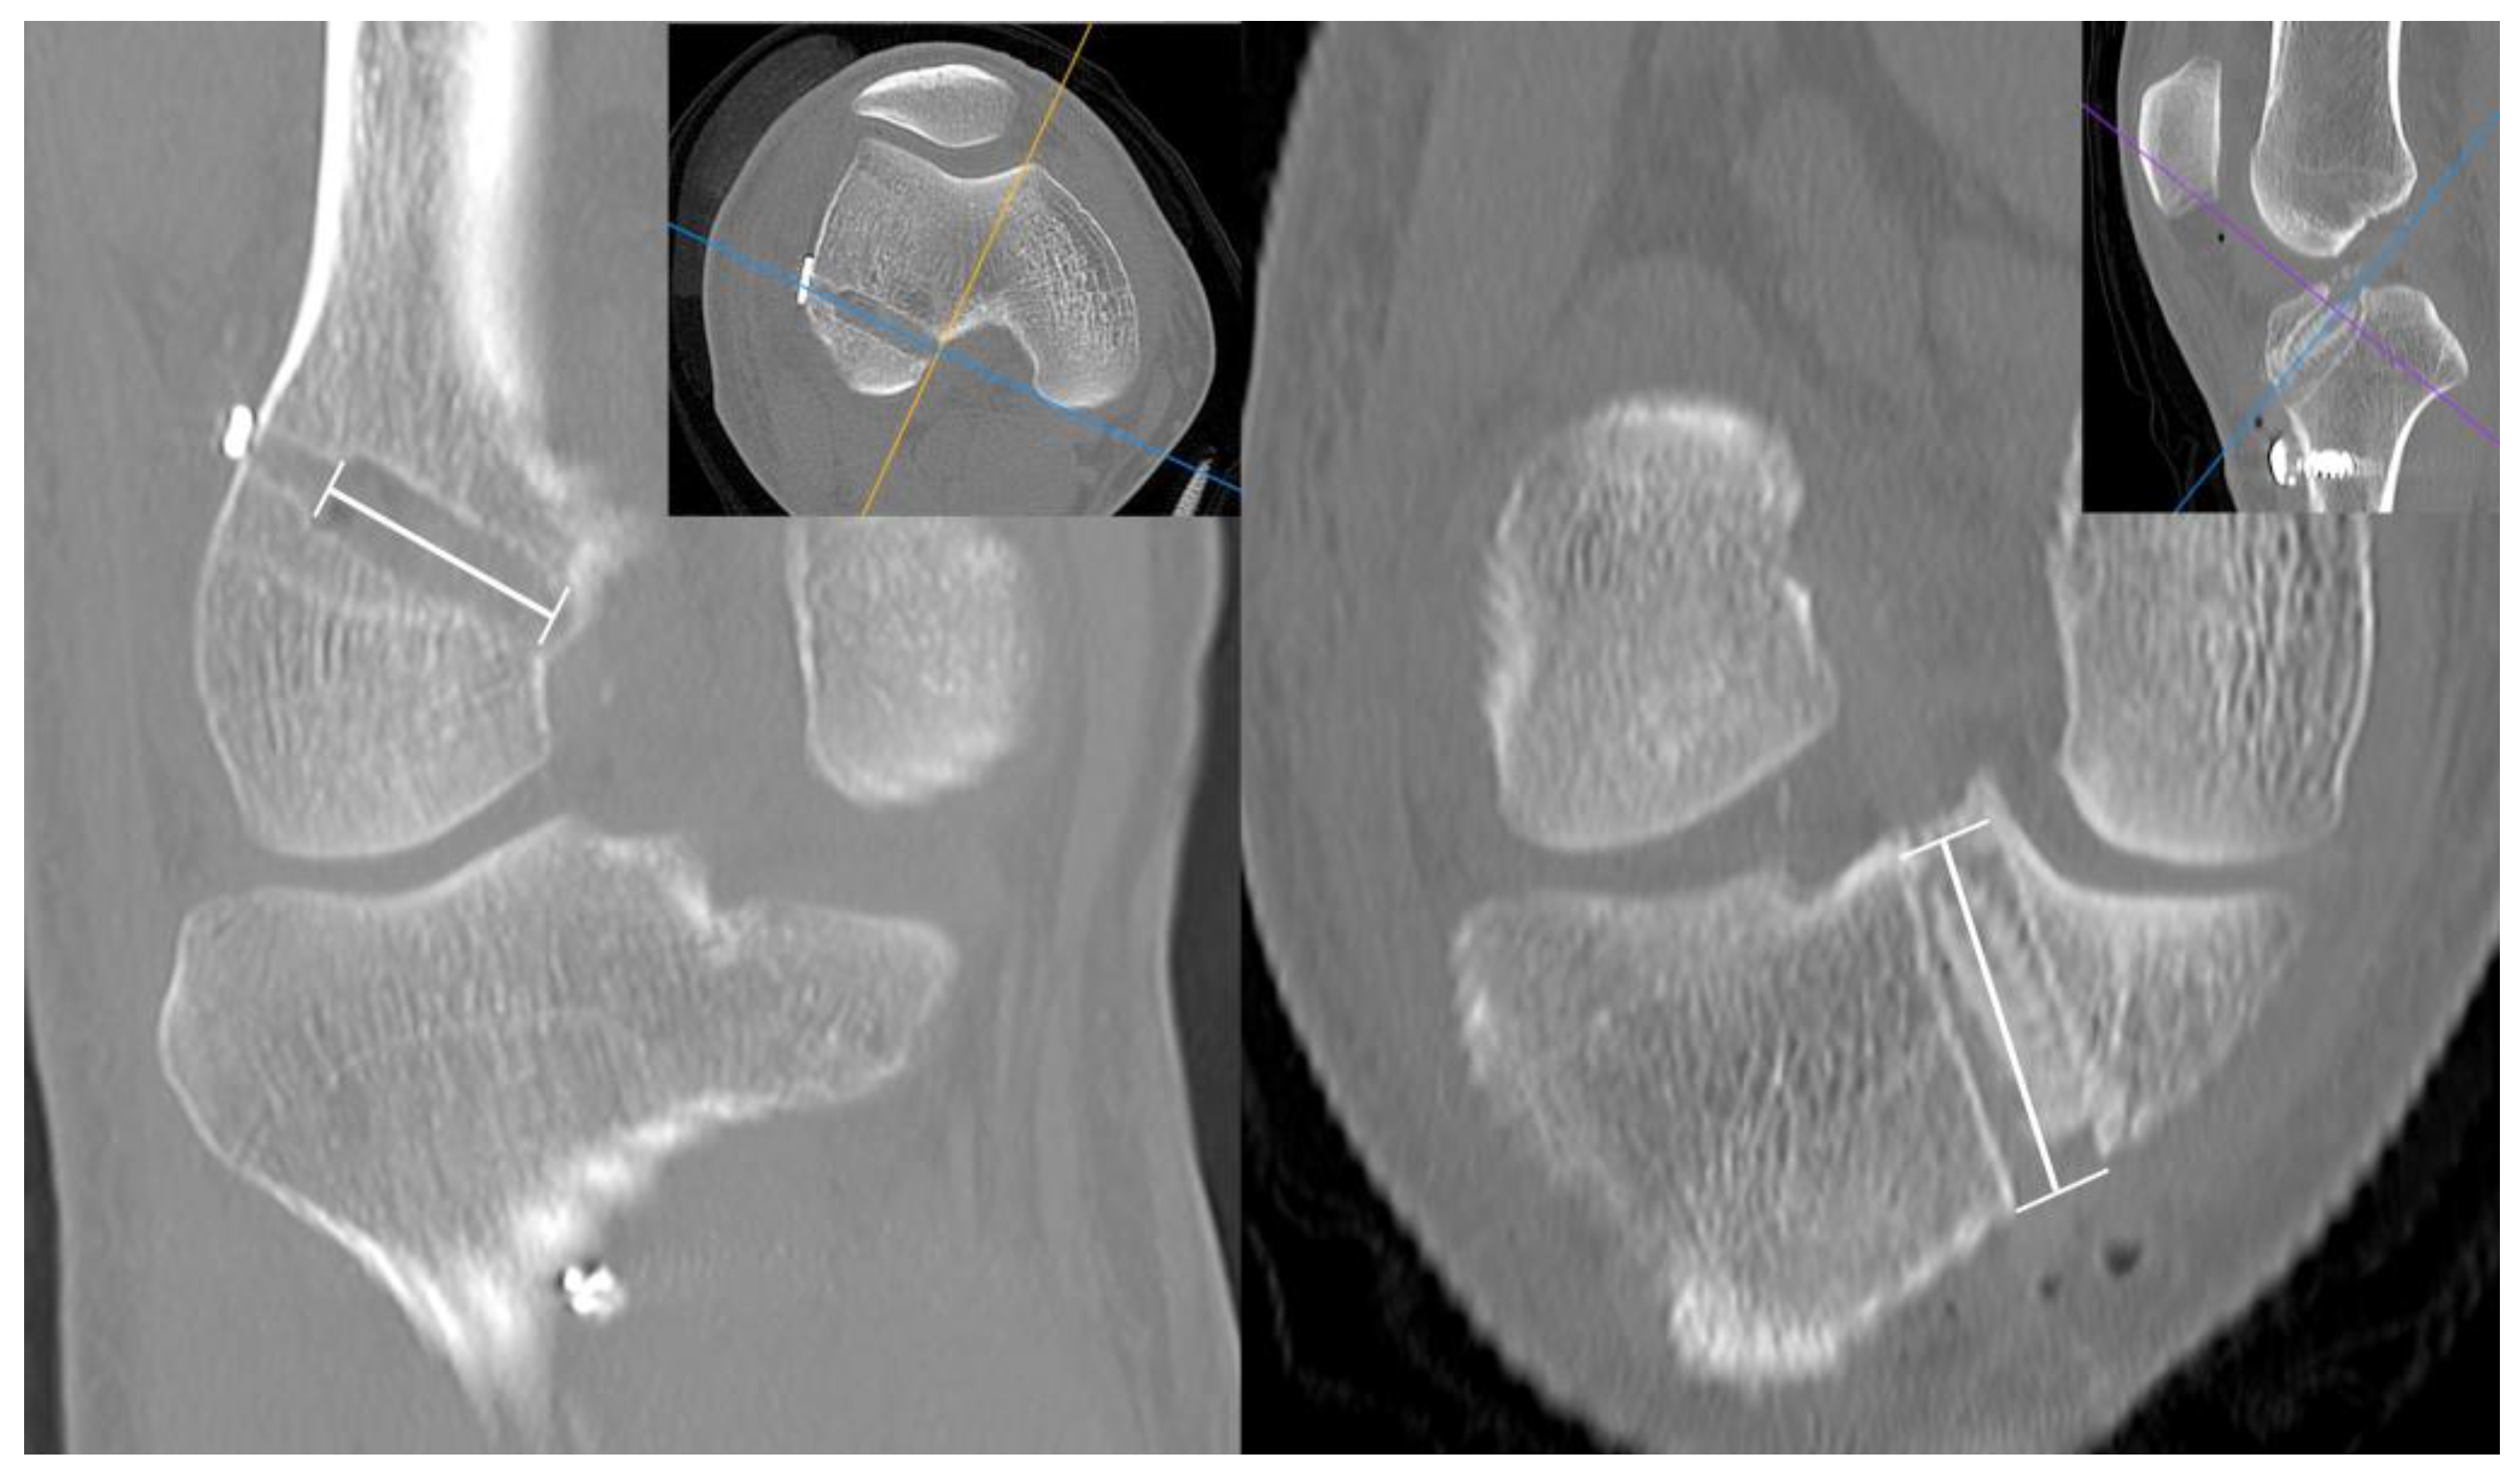

CT was also used to measure the femoral and tibial tunnel lengths. Images of the oblique plane which best visualized the long axis of the tunnels were analyzed using the Horos medical image viewer (version 3.3.5; Horos Project, New York, U.S.) [11] (Figure 6).

Figure 6.

Measurement of the length of femoral and tibial tunnel on CT scan.